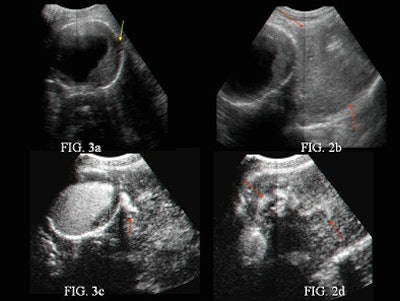

| Baseline sonogram (a-b) and contrast-enhanced US scan (c-d) of an abdominal aortic aneurysm. The baseline sonogram shows focal interruption of aneurysm (small hypoechoic focus adjacent to the aneurysm, yellow arrow) and left-sided retroperitoneal hematoma (red arrows). |